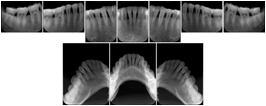

2. A patient requests cosmetic surgery to enhance their facial appearance. The case requires consultation between an orthodontist in New York and an oral surgeon in California. The cephalometric series of 2D projections constructed from the volumetric CT data that is used for the discussion is arranged by a Structured Display for transfer between the two practitioners.

Cephalometric Series Structured Display

Figure OO-2. Cephalometric Series Structured Display